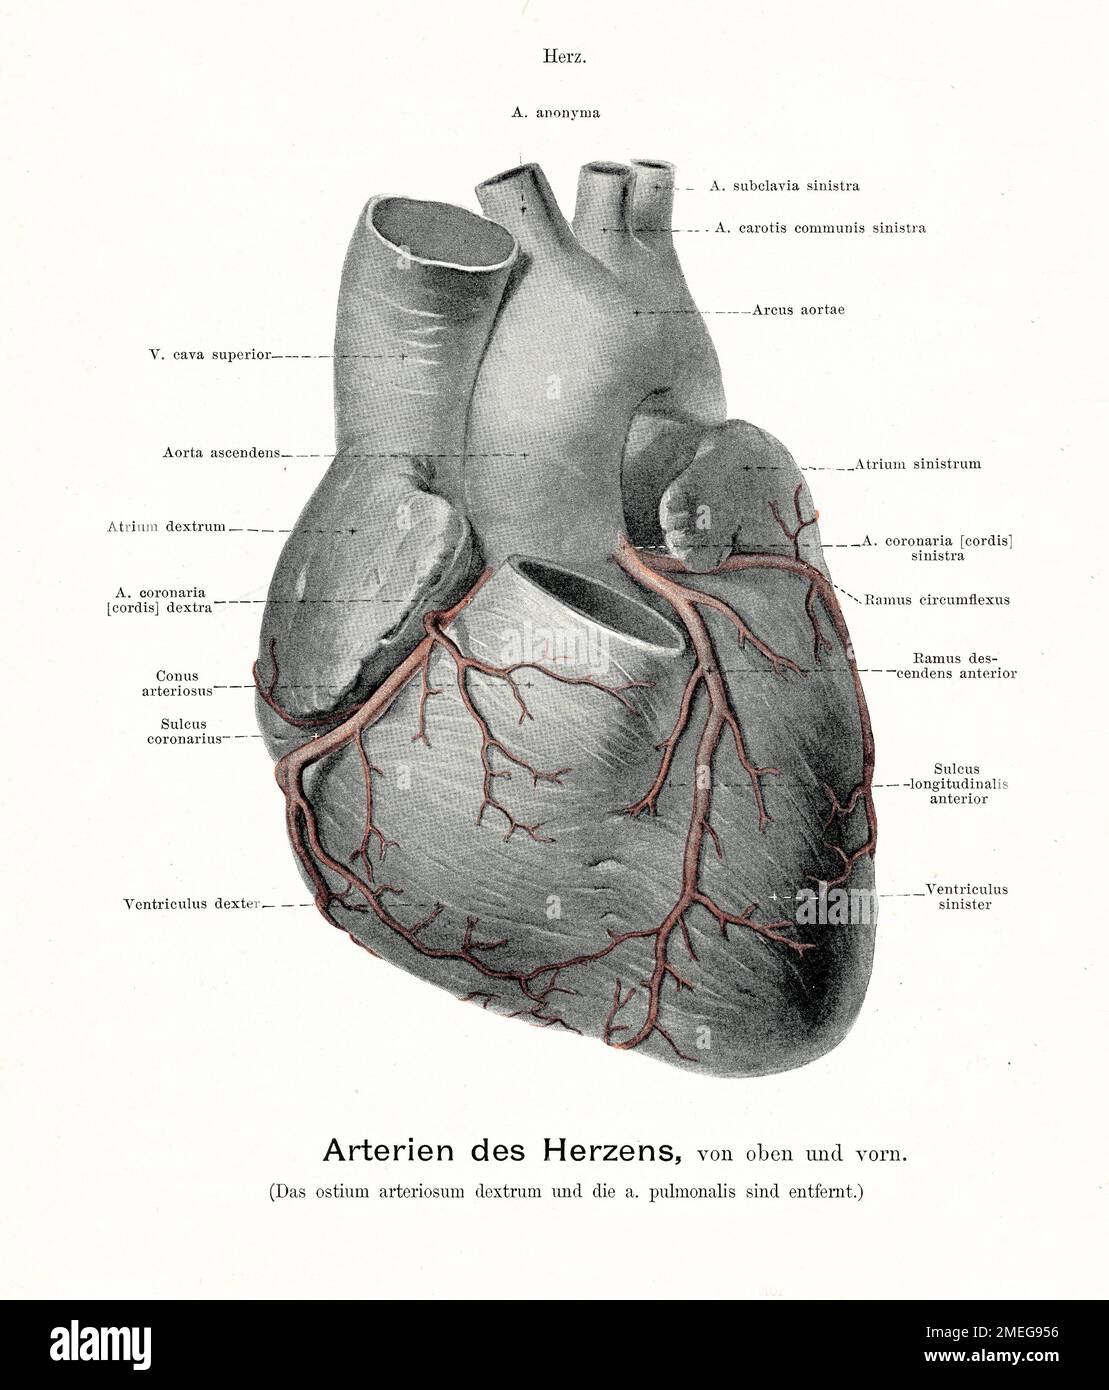

Vintage illustration of anatomy of the arteries of the heart, with German anatomical descriptions Stock Photohttps://www.alamy.com/image-license-details/?v=1https://www.alamy.com/vintage-illustration-of-anatomy-of-the-arteries-of-the-heart-with-german-anatomical-descriptions-image508064290.html

Vintage illustration of anatomy of the arteries of the heart, with German anatomical descriptions Stock Photohttps://www.alamy.com/image-license-details/?v=1https://www.alamy.com/vintage-illustration-of-anatomy-of-the-arteries-of-the-heart-with-german-anatomical-descriptions-image508064290.htmlRM2MEG956–Vintage illustration of anatomy of the arteries of the heart, with German anatomical descriptions